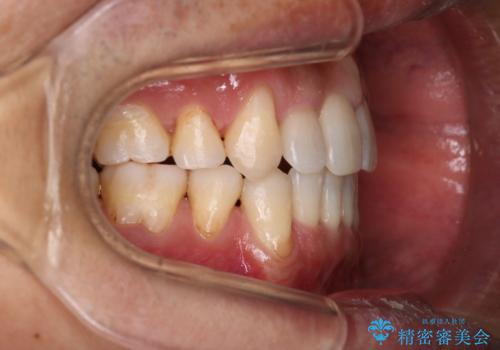

- 治療計画

叢生量が大きいため、上下顎両側4番を抜歯しました。矯正治療による歯肉退縮の著しい悪化もなく、主訴であるガタつきも改善できました。